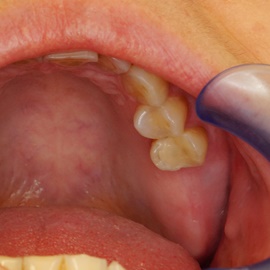

Skrócony łuk zębowy, kończący się na trójce. Blade atroficzne tkanki miękkie, relif dziąsła typu A, kość o małej gęstości, słabo ubeleczkowana i o kiepskim ukrwieniu. Niekorzystne warunki do odbudowy kości. Okres leczenia 1,5 roku, po odbudowie kości, zadowalający wynik końcowy w żuchwie, czas na korektę płaszczyzny zgryzowej.